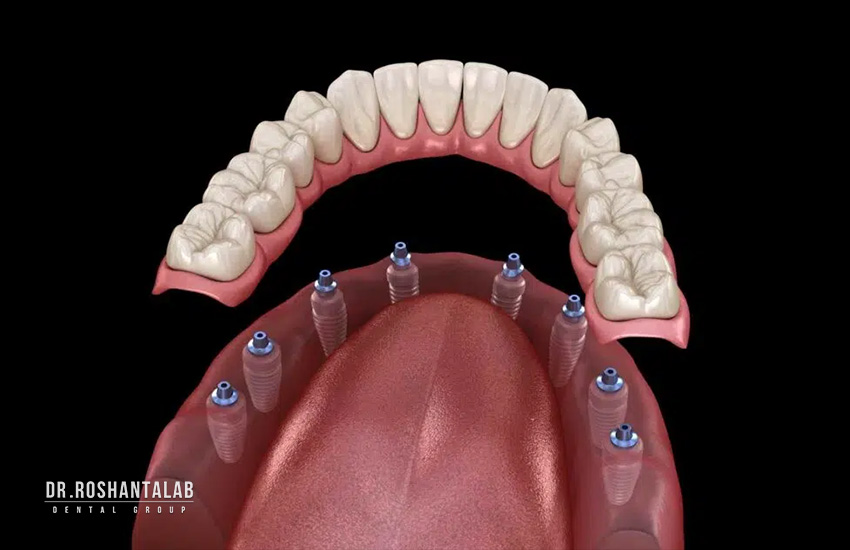

ایمپلنت کامل دندان که در ادبیات علمی با نامهای Full Mouth Dental Implant Reconstruction، Full Arch Fixed Implant Prosthesis یا Full Mouth Rehabilitation with Implants شناخته میشود، پیشرفتهترین، دائمیترین و طبیعیترین روش جایگزینی تمام دندانهای از دست رفته در هر دو فک بالا و پایین به صورت همزمان یا جداگانه است.

در این روش، به جای اینکه برای هر دندان از دست رفته یک ایمپلنت جداگانه کاشته شود (که در مجموع ۲۸ تا ۳۲ ایمپلنت نیاز داشت و هزینه و زمان بسیار بالایی میطلبید)، تنها با استفاده از ۸ تا ۱۶ پایه ایمپلنت تیتانیومی یا زیرکونیوم-تیتانیومی (معمولاً ۴ تا ۸ پایه در هر فک)، یکدست، یک پروتز ثابت کامل شامل ۲۴ تا ۲۸ دندان (۱۲ تا ۱۴ دندان در هر فک) به صورت پل یا بریج کامل روی این پایهها پیچ یا چسبانده میشود.

- ۴ پایه در هر فک (۲ عمودی جلو + ۲ زاویهدار عقب تا ۴۵ درجه)

- ۶ پایه در هر فک

- ۸ پایه عمودی در هر فک